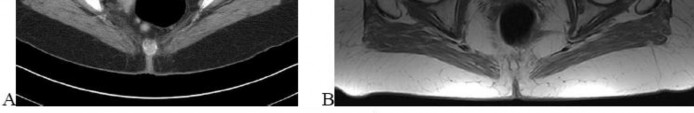

A 65-year-old male who underwent a cementless total hip arthroplasty (THA) 15 years ago presents with new-onset thigh pain. Radiographs reveal eccentric positioning of the femoral head within the acetabular shell and large retroacetabular and proximal femoral radiolucencies.

What is the primary biological mediator released by macrophages that directly stimulates osteoclastogenesis and is responsible for the observed bone loss?

Explanation

The radiograph demonstrates particle-induced osteolysis, secondary to polyethylene wear debris. When macrophages phagocytose these particles, they release pro-inflammatory cytokines, most notably TNF-a, IL-1, and IL-6. These cytokines stimulate the RANK/RANKL pathway, activating osteoclasts and leading to significant periprosthetic bone loss. IL-10 and IL-4 are anti-inflammatory cytokines, while IFN-y actually inhibits osteoclastogenesis.